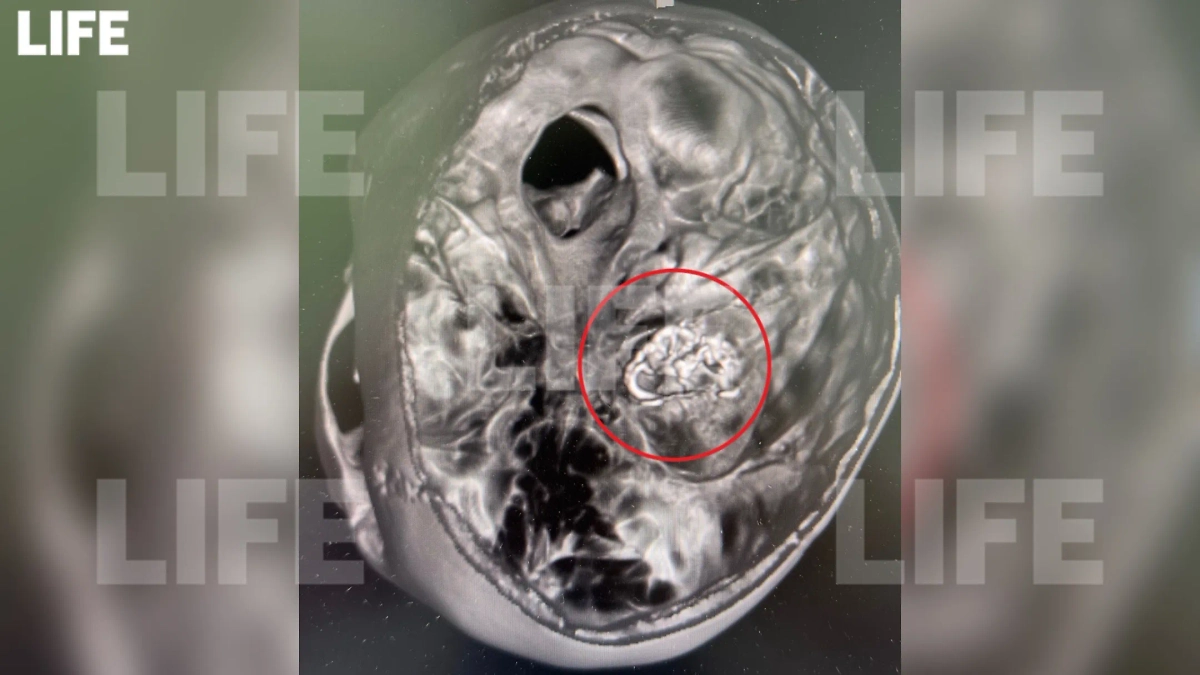

В Детском клиническом центре имени Рошаля успешно спасли 16-летнюю девушку, которая поступила с признаками геморрагического инсульта. Обследование показало наличие кровоизлияния в мозг, вызванного разрывом сосуда, а также артериовенозную мальформацию — патологию, при которой мелкие вены и артерии переплетаются, образуя «сосудистый клубок».

Обследование выявило кровоизлияние в мозг из-за лопнувшего сосуда и артериовенозную мальформацию сосудов головного мозга. Фото предоставлено Life.ru пресс-службой медучреждения

Это патология, при которой вены и артерии небольшого диаметра, переплетаясь друг с другом, образуют «сосудистый клубок». Фото предоставлено Life.ru пресс-службой медучреждения